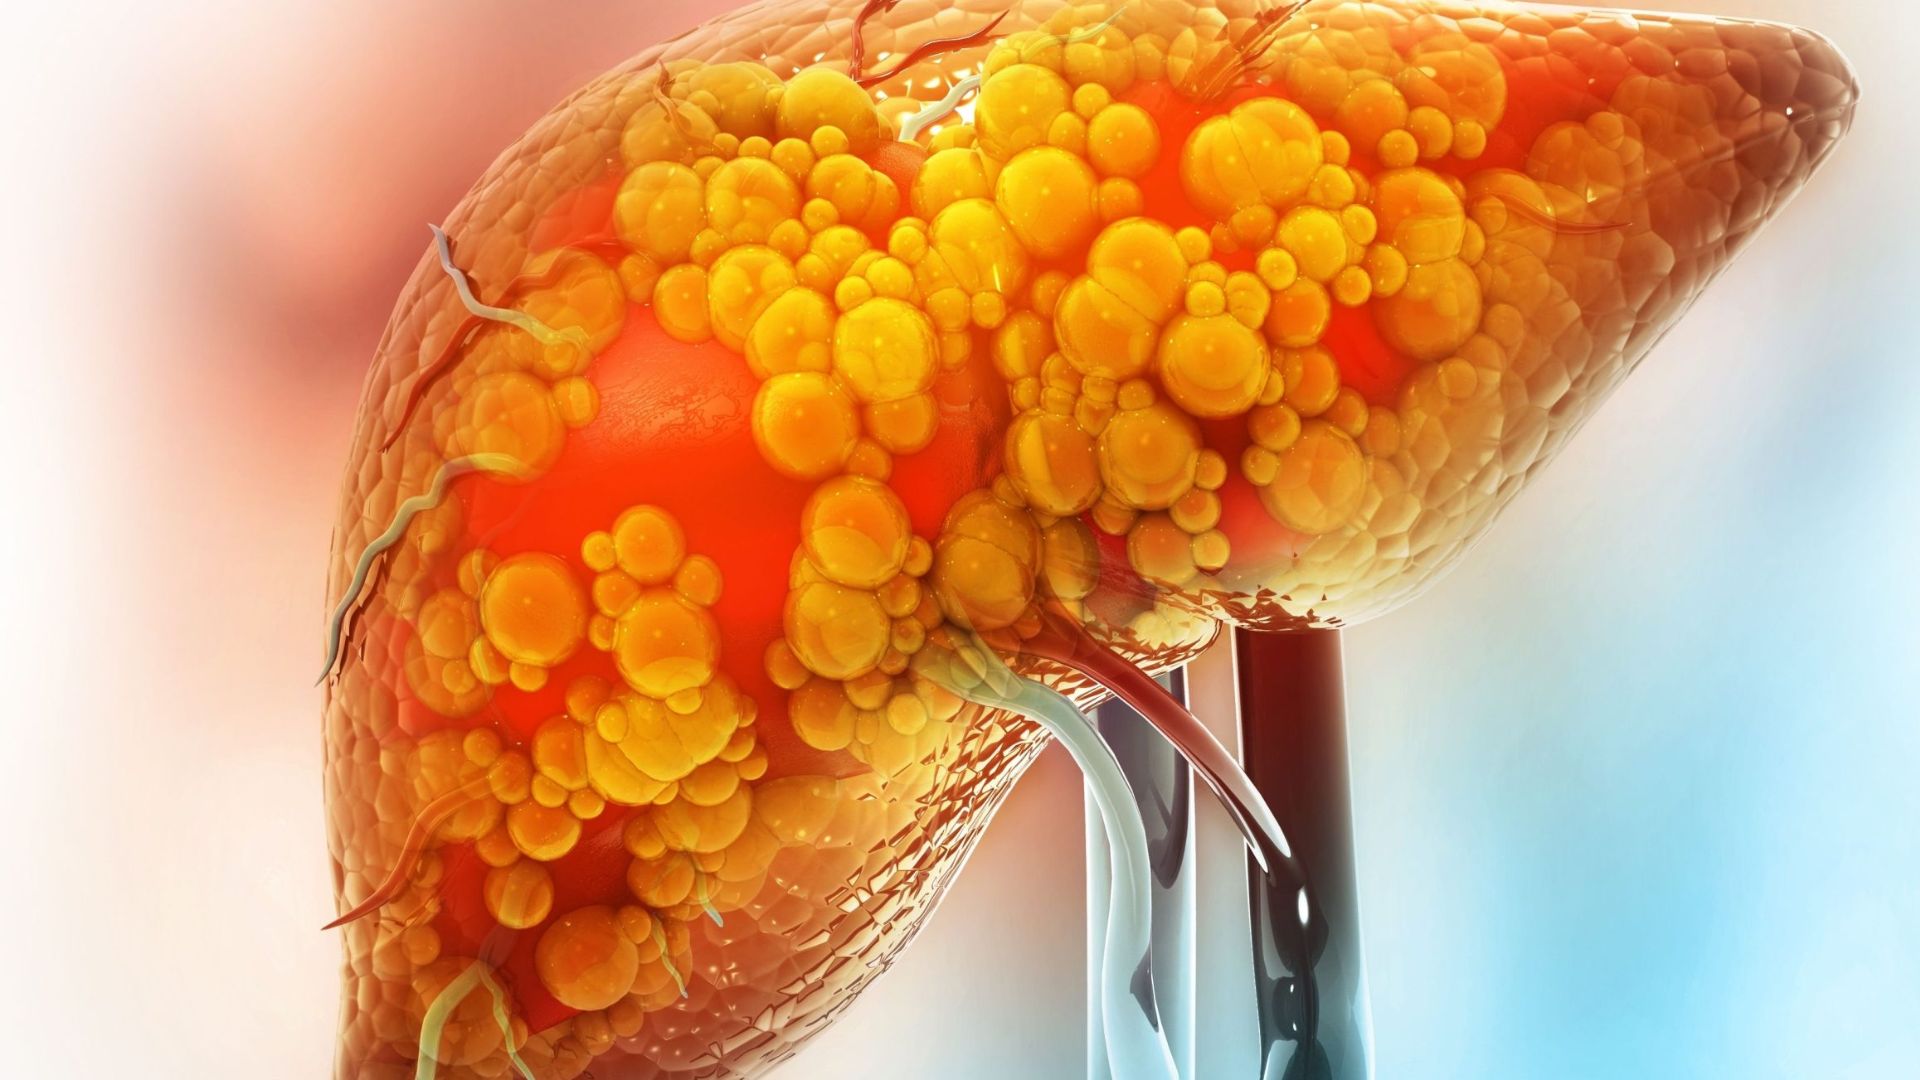

Đồ chiên rán là món ăn hấp dẫn và quen thuộc trong khẩu phần của nhiều người. Tuy nhiên, việc tiêu thụ quá nhiều thực phẩm nhiều dầu mỡ có thể gây ra những ảnh hưởng nhất định đến sức khỏe, đặc biệt là đối với gan – cơ quan đóng vai trò quan trọng trong quá trình chuyển hóa và giải độc của cơ thể.